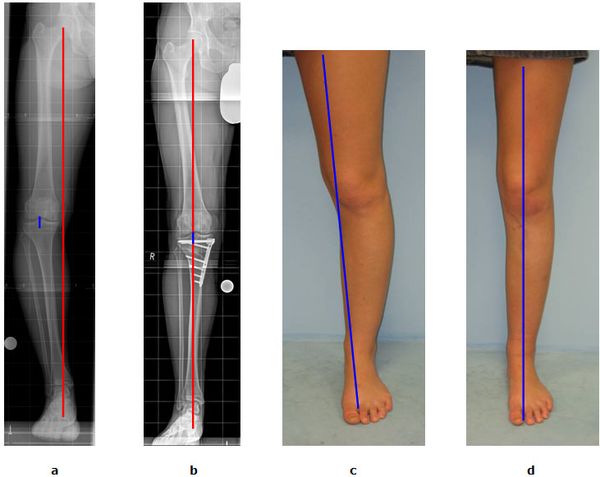

Abb.1: a Die mechanische Beinachse (rote Linie) verläuft nicht mehr durch die Kniegelenksmitte (blaue Linie) sondern ist nach Innen verlagert. Es handelt sich um eine O-Bein Fehlstellung. Der Innere Gelenkspalt ist bereits hochgradig verschmälert (Varusgonarthrose).

b Durch eine Kniegelenksnahe Umstellung des Schienenbeins

(Tibiakopfosteotomie)verläuft die mechanische Beinachse wieder mittig. Die blaue und rote Linie decken sich. Der Innere Gelenkspalt ist entlastet.

c O-Bein Stellung vor der Operation.

d Die Begradigung durch den Eingriff ist offensichtlich.